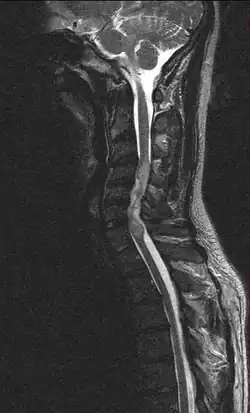

Zespół Froina – w badaniu płynu mózgowo-rdzeniowego, współistnienie ksantochromii, wysokiego poziomu białka i braku pleocytozy. Występuje w bloku przepływu płynu mózgowo-rdzeniowego, wywołanym np. przez guz rdzenia ("zastoinowy płyn mózgowo-rdzeniowy").